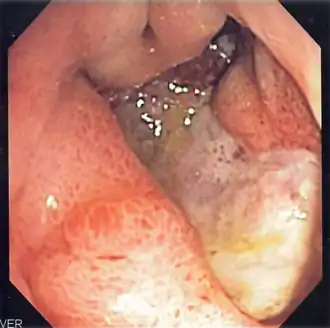

Úlcera péptica é uma lesão no revestimento do estômago, no duodeno ou, raramente, na parte final do esófago.[1][7] Uma úlcera no estômago denomina-se úlcera gástrica, enquanto que uma no duodeno se denomina úlcera duodenal. Os sintomas mais comuns são acordar de noite com dor na parte superior do abdómen ou dor na parte superior do abdómen que melhora ao comer. A dor é muitas vezes descrita como ardor ou dor ligeira constante. Entre outros possíveis sintomas estão a eructação, vómitos, perda de peso ou perda de apetite. Cerca de um terço das pessoas não manifesta sintomas.[1] Entre as possíveis complicações estão a hemorragia gastrointestinal, perfuração gastrointestinal e obstrução da saída gástrica. Cerca de 15% das pessoas apresentam hemorragia.[2]

As causas mais comuns são a bactéria Helicobacter pylori e os anti-inflamatórios não esteroides.[1] Entre as outras possíveis causas está o fumar, o stresse devido a doença grave, a doença de Behçet, a síndrome de Zollinger-Ellison, a doença de Crohn e a cirrose hepática.[1][3] As pessoas idosas são mais sensíveis aos efeitos dos anti-inflamatórios não esteroides. O diagnóstico pode ser suspeitado com base nos sintomas e confirmado com endoscopia ou ingestão de bário. A presença de H. pylori pode ser confirmada com análises ao sangue que detectam a presença de anticorpos, com um teste rápido da urease, com exames às fezes para observar sinais da bactéria ou com uma biópsia do estômago. Entre outras doenças que produzem sintomas semelhantes à úlcera péptica estão o cancro do estômago, a doença arterial coronária, a inflamação do revestimento do estômago ou cálculos na vesícula.[1]

A dieta não tem um papel significativo nem na causa nem na prevenção de úlceras.[8] O tratamento consiste em deixar de fumar, deixar de tomar anti-inflamatórios não esteroides, em deixar de ingerir bebidas alcoólicas e em medicamentos para diminuir a acidez do estômago. Os medicamentos usados são geralmente ou um inibidor da bomba de protões ou um antagonista do receptor H2 ao longo de quatro semanas recomendadas de tratamento inicial.[1] As úlceras causadas por H. pylori são tratadas com uma combinação de medicamentos como a amoxicilina, claritromicina e um inibidor da bomba de protões. Como a resistência antibiótica está a aumentar, o tratamento com antibióticos nem sempre é eficaz.[4] As úlceras hemorrágicas podem ser tratadas com cirurgia por endoscopia, sendo usada cirurgia aberta apenas nos casos em que a endoscopia não foi eficaz.[2]